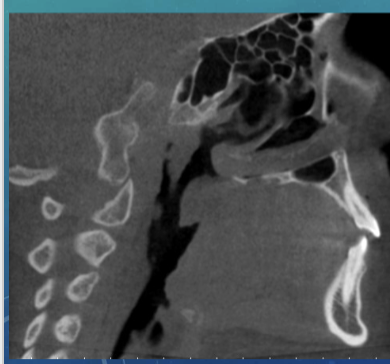

axial plane

sagittal plane

multiplanar reconstruction/ reformation

commons uses of 3D imaging

endo assessment

airway and sinus analysis

eval of TMJ disorders

trauma eval